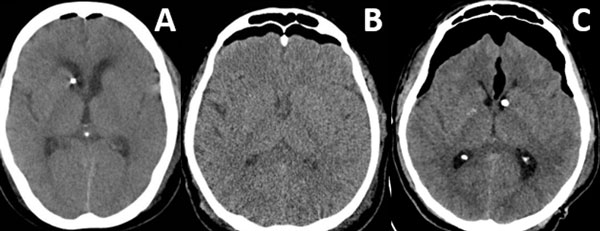

Patrones y grados de NE: NE subdural (Figura 1), se clasificó en 3 grados: leve (menor al espesor óseo), moderado (entre una vez y dos veces el espesor óseo) y severo (dos o más veces el espesor óseo). NE subaracnoideo (Figura 2), se clasificó en 3 grados: leve (confinado a cisternas basales), moderado (cisternas supratentoriales predominio unilateral), severo (generalizado). NE ventricular (Figura 3), se clasificó en: leve (en IV y/o III ventrículo), moderado (alcanzó VL), severo (alcanzó y dilató los VL).

Figura 1. Neumoencéfalo subdural. A) Leve. B) Moderado. C) Severo.